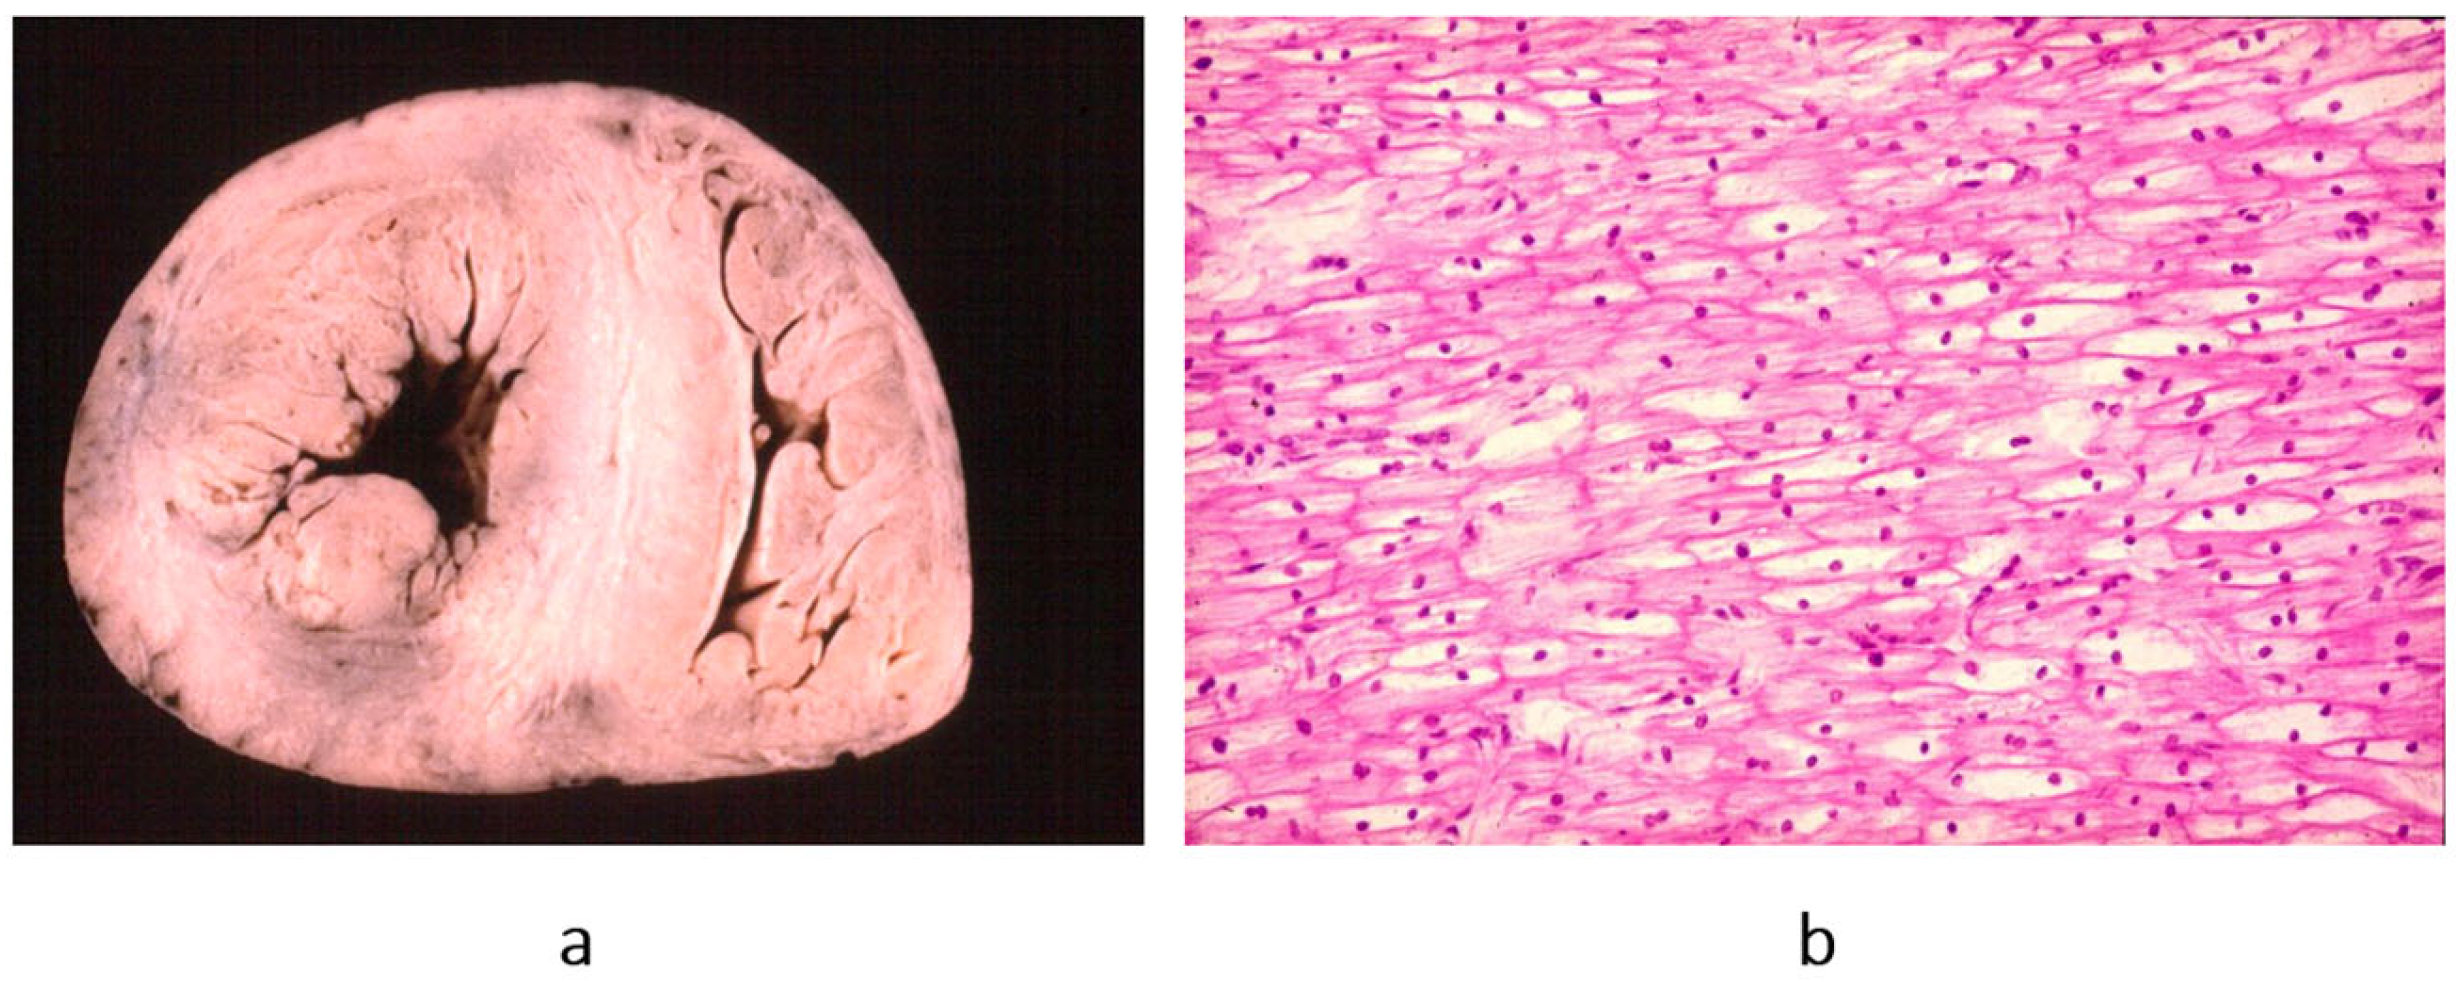

Concerning dilated cardiomyopathy, ventricular dilatation (Figure 2a and Figure 4a) can be due to poor contractility caused by myocytolysis (Figure 4b) or previous viral myocarditis with scarring from necrosis (Figure 5).

Figure 4. Example of a heart with dilated cardiomyopathy, gross view (a), and myocytolysis of cardiomyocytes on histology (b), haematoxylin–eosin stain. From [3] with permission.

Figure 5. Another type of dilated cardiomyopathy (a) with severe, non-ischemic myocardial fibrosis (b). The patient previously had viral myocarditis, which accounted for myocyte necrosis and scarring. Azan Mallory stain. From [3] with permission.